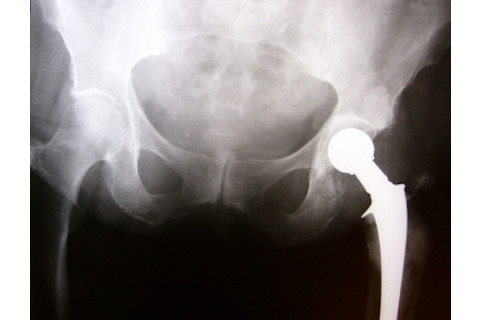

Damage to the joint from sever arthritic inflammation often requires a hip replacement. | NULL